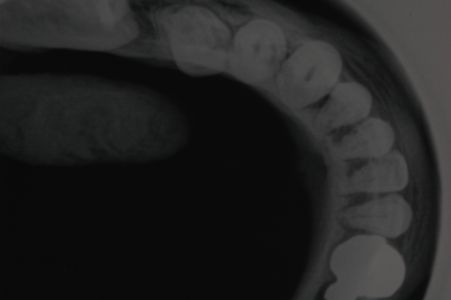

Sottoponiamo il paziente ad accertamenti diagnostici di tipo radiologico, sottoponendolo a ortopantomografia delle arcate dentarie

da cui si intravede una formazione radiopaca di forma ovalare nella regione mandibolare destra, all'ingrandimento

si rileva la continuità dei bordi. Essendo l'O.P.T. una RX bidimensionale sottoponiamo il paziente ad una RX occlusale da cui rileviamo che la formazione è dispersa nei tessuti molli del pavimento linguale.